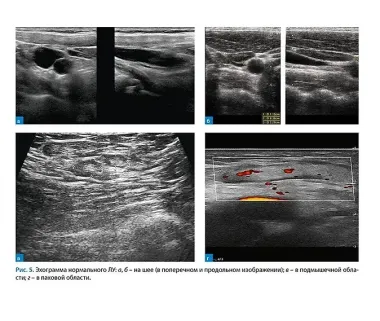

В книге обсуждаются возможности высокочастотной ультразвуковой диагностики оценивать структурную перестройку поверхностных лимфатических узлов. Приводятся данные об особенностях физиологии, нормальной и ультразвуковой анатомии лимфатических узлов в различных регионарных зонах. Ультразвуковые признаки перестройки лимфатических узлов рассматриваются на моделях доброкачественных и злокачественных поражений. Обсуждаются варианты перестройки на фоне инволюции и при других доброкачественных процессах. Эхограммы сопровождаются текстовыми комментариями и поясняются графическими рисунками и схемами. Разбор структурной перестройки в лимфатических узлах проводится в свете дифференциальной диагностики доброкачественных и злокачественных процессов. Прослеживаются различия в детализации структурных элементов лимфатических узлов при ультразвуковом исследовании датчиками высоких и сверхвысоких частот. Для закрепления информации предложена уникальная форма индивидуального тренинга-обучения по распознаванию визуальных образов доброкачественной и злокачественной перестройки в лимфатических узлах. Предлагается подбирать эхограммы и рисунки в виде наклеек при решении закрепляющих обучение примеров и задач на внимание и логику. Ответы представлены в отложенной во времени форме через систему QR-кодов как приглашение к самостоятельному решению задания. Для иллюстрации необходимости обладания врачом-диагностом не только узкопрофессиональными знаниями, но и информацией о клинико-анатомических особенностях конкретного органа предлагается вторая часть книги, где на клиническом примере разбираются общность и различия ультразвуковых проявлений метастаза в аксиллярный лимфатический узел и первичной злокачественной опухоли молочной железы с локализацией в добавочной ткани подмышечной области.ID Продукта